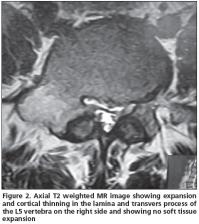

A 21 year-old male patient admitted to our clinic with low back pain persistent to medication for the last 3 years. He was first referred to physical medicine and rehabilitation department and then to a neurosurgery department after several visits because of persistent pain. He had no history of trauma. His pain was not aggravated by coughing, standing or sitting; and the pain was not relieved by salicylates or NSAIDs. Whole blood count (CBC), erythrocyte sedimentation rate (ESR) and rheumatoid factor (RF) were found within normal limits. Physical examinations were found normal except the tenderness extending from T12 to L5 associated with paravertebral muscle spasm. His lumbosacral CT was taken and then a tumoral mass was noticed enlarging transverse process and right lamina of L5 vertebrae with probable diagnosis of osteoblastoma or osteoid osteoma. The mass had a lytic nature with well defined osteosclerotic boundaries and facet joints were normal (Figure 1). An MRI was taken to evaluate the soft tissue expansion which showed no affection (Figure 2). A CT-guided biopsy resulted with unsatisfactory sample gathering. Then he has taken to the operation theatre and curettage and frozen section was performed since the probable diagnosis was osteoblastoma. After confirmation of benign tumoral process, the cavity was filled with allograft. The histopathological examination confirmed the diagnosis of osteoblastoma. Following surgery, the patient was asymptomatic; there was no neurological dysfunction and no residual pain or discomfort. No recurrence has been observed for four years.

Osteoblastomas are composed of an abundantly vascular connective-tissue stroma with active production of osteoid and primitive woven bone. A central lucency with a variable zone of peripheral sclerosis is the typical pattern; osteolysis and mass effect are frequently present[3]. It can be seen in any area of skeleton but it is the only benign tumor which shows primary affection to spinal column, and both the body and posterior arch of vertebrae[3,5]. The diagnostic radiographic feature is usually a single, round area of osteolysis which expands the bone and it is not always with well defined boundaries. Marked osteolysis may be seen around the lesion which is not as extensive as in osteoid osteoma[6]. Histologically, osteoid osteomas and osteoblastomas are similar. Their most remarkable difference is: osteoblastoma has an unlimited growth potential with a capability of malignant transformation and is larger in size (usually larger than 2 cm). Plain radiography and CT findings are similar, including radiolucent nidus, matrix calcifications, and accompanying bony sclerosis. Differentiation is made on the basis of size, and the larger lesions are typically categorized as osteoblastoma, but osteoblastoma detected early and not exceeding a diameter of 2 cm makes the distinction difficult. Then, clinical presentation plays an important role in the diagnosis. Osteoblastomas are known to have a high incidence of neurological deficit. Neurologic involvement has been reported in 25–50% of patients. The tumor located in the spine can cause neurological symptoms. The case presented here had no neurological deficit.